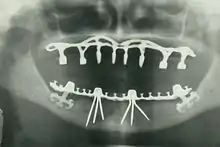

Implant retained fixed bridge or implant supported bridge

An implant supported bridge (or fixed denture) is a group of teeth secured to dental implants so the prosthetic cannot be removed by the user. They are similar to conventional bridges, except that the prosthesis is supported and retained by one or more implants instead of natural teeth. Bridges typically connect to more than one implant and may also connect to teeth as anchor points. Typically the number of teeth will outnumber the anchor points with the teeth that are directly over the implants referred to as abutments and those between abutments referred to as pontics. Implant supported bridges attach to implant abutments in the same way as a single tooth implant replacement. A fixed bridge may replace as few as two teeth (also known as a fixed partial denture) and may extend to replace an entire arch of teeth (also known as a fixed full denture). In both cases, the prosthesis is said to be fixed because it cannot be removed by the denture wearer.[15]